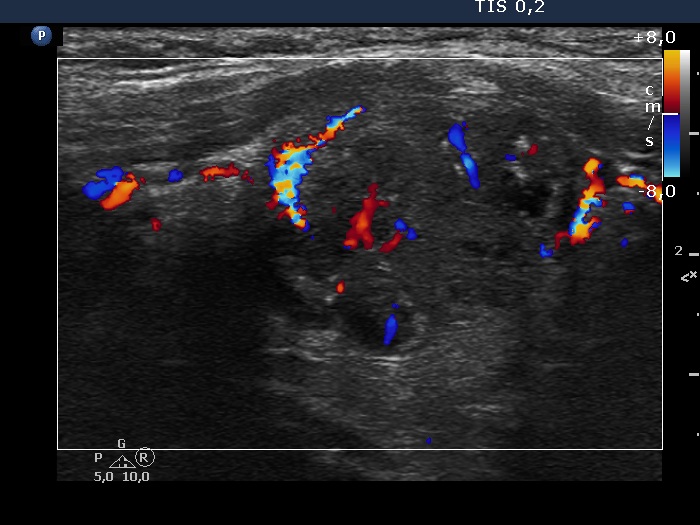

Follow-up investigation 7 years after the first visit (ultrasonographic picture 9)

Left lobe, longitudinal scan, color Doppler mode. The nodule presents intranodular blood flow.